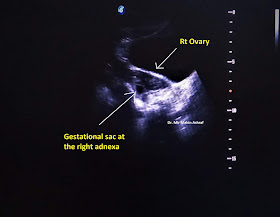

1. Uterus is bulky. An irregular fluid collection without any fetal pole is noted within the endometrial cavity representing pseudo-gestational sac. (Not well shown in the figures).2. Right tubo-ovarian region shows an irregular small gestational sac of 8.8 mm diameter, surrounded by an irregular thick wall forming donut sign, without any feta pole inside.

3. Color Doppler shows relatively low resistance pattern of arterial supply (RI: 0.5) around the sac along with peripheral 'Ring of Fire' appearance.

Ruptured right adnexal ectopic pregnancy.Scanning was done on the 06.06.18 at 3-4am.